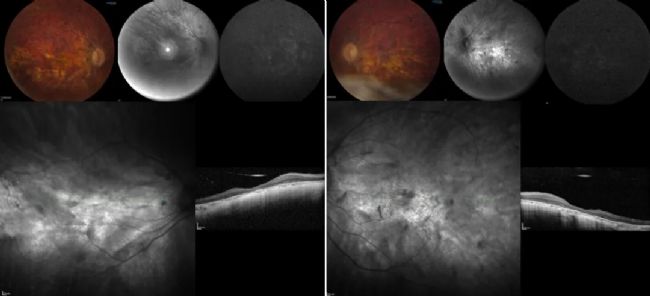

術前 OCT 和藍色自發(fā)熒光眼底圖像顯示光感受器僅出現(xiàn)在中心凹區(qū)域和對稱的左眼。

圖 1:右眼(左圖)和左眼(右圖)的術前 OCT 和藍色自發(fā)熒光眼底圖像。